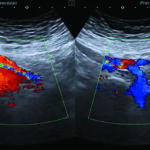

Fig. 3. Examen ecográfico abdominal, se observa compresión de la vena renal izquierda entre la aorta y la arteria mesentérica superior (mide 3,1 mm a nivel del compás y 8,1 mm en el segmento proximal al riñón izquierdo).

Fig. 7. Doppler color de venas iliacas internas, demostrando flujo reverso del lado izquierdo como signo indirecto de compresión en la VICI.

Hallazgos imagenológicos. En el eco Doppler ginecológico por vía transvaginal se observa varicocele pelviano (Fig. 5). En el eco Doppler abdominal se visualiza vena iliaca común izquierda (VICI), la que mide 2.4 mm antes de pasar entre a la arteria iliaca común derecha (AICD) y la columna y 8.2 mm en el segmento distal (Fig. 6). Estudio que corresponde en primera instancia a síndrome de May Thurner.

Se evidencia también flujo reverso en la vena iliaca interna izquierda como signo indirecto de compresión de la VICI (Fig. 7).